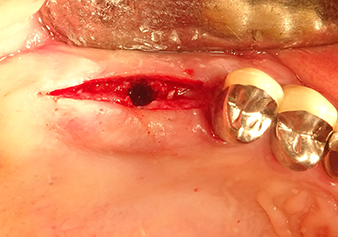

Implant bed preparation and augmentation

Following an intermediate check (Fig. 4) a further preparation step was performed (Fig. 5). Afterwards, the hydraulic Z35P instrument was used to lift the membrane to the desired position (Fig. 6 and 7). This was followed by further piezosurgical preparation of the implant bed, concluded with a rotary bur and shoulder milling cutter up to the implant diameter of 4.8 mm. Before the implant was inserted, the augmentation material (particle size approx. 0.8-1.6 mm) was introduced underneath the Schneiderian membrane (Fig. 8).

Implantation and prosthetic restoration